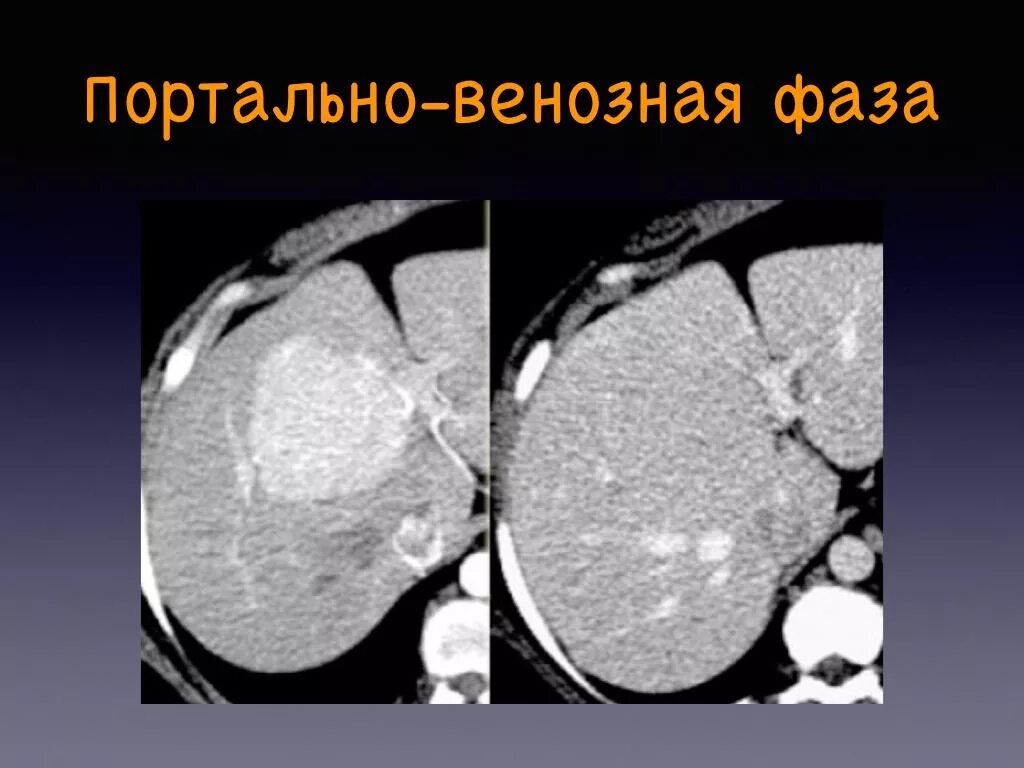

Фазы кт